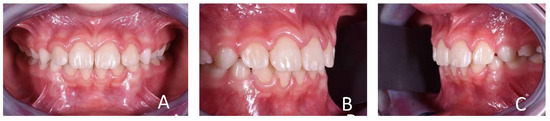

3.1. Clinical Case #1

3.2. Clinical Case #2

3.3. Clinical Case #3

3.4. Clinical Case #4